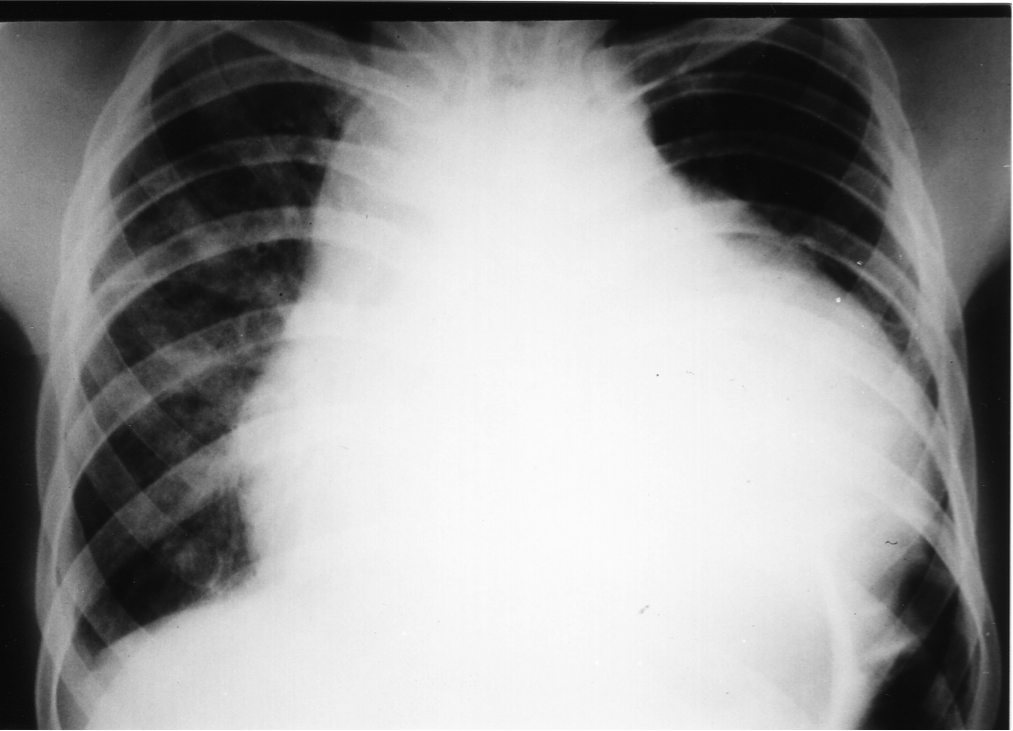

This middle-aged man, a sailor, was transferred to the hospital directly after his ship sailed into port. He had been ill for 2 months, with low-grade fever, weight loss of almost 8 kg, and shortness of breath upon exertion. His chest X-ray is shown below:

Along with the previously-described ECG changes, a diagnosis of cardiac tamponade (from massive pericardial effusion) was made, which was confirmed via urgent trans-thoracic echocardiography. Routine blood investigations performed at the emergency department revealed the following:

He underwent urgent pericardiocentesis, with hemoserous fluid aspirated.